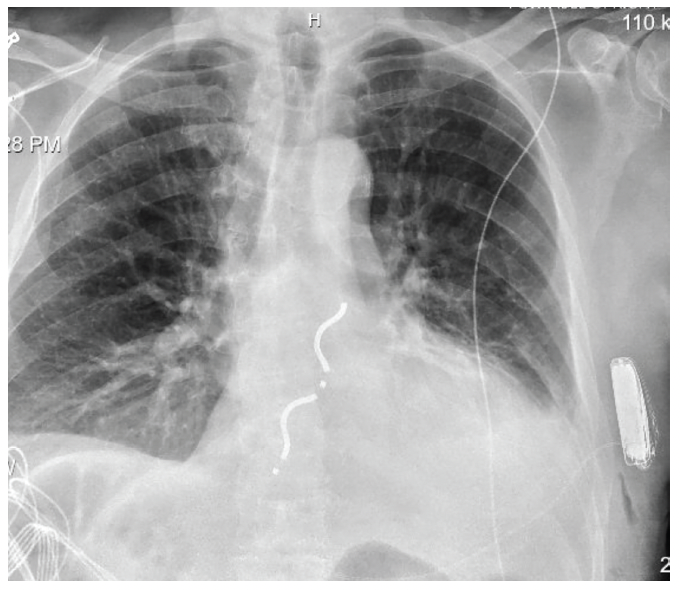

The patient was then brought back to the EP lab for device exchange. An Aurora EV-ICD (Medtronic) was implanted and the patient’s existing S-ICD system was removed (Figure 2). He received inappropriate ATP for atrial flutter. Device settings were adjusted to avoid atrial oversensing.